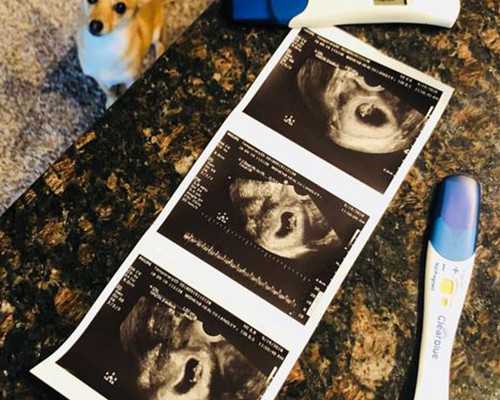

- 驗孕試紙什么時候能測出懷孕?

- 驗孕試紙準不準?什么時候用最合適

- 驗孕棒怎么用才準?手把手教你正確操作

- 早早孕試紙怎么用?這些細節(jié)你得知道

- 早孕試紙怎么用和看結(jié)果?簡單幾步教會你

- 早孕試紙的正確用法,這些細節(jié)你可能不知道